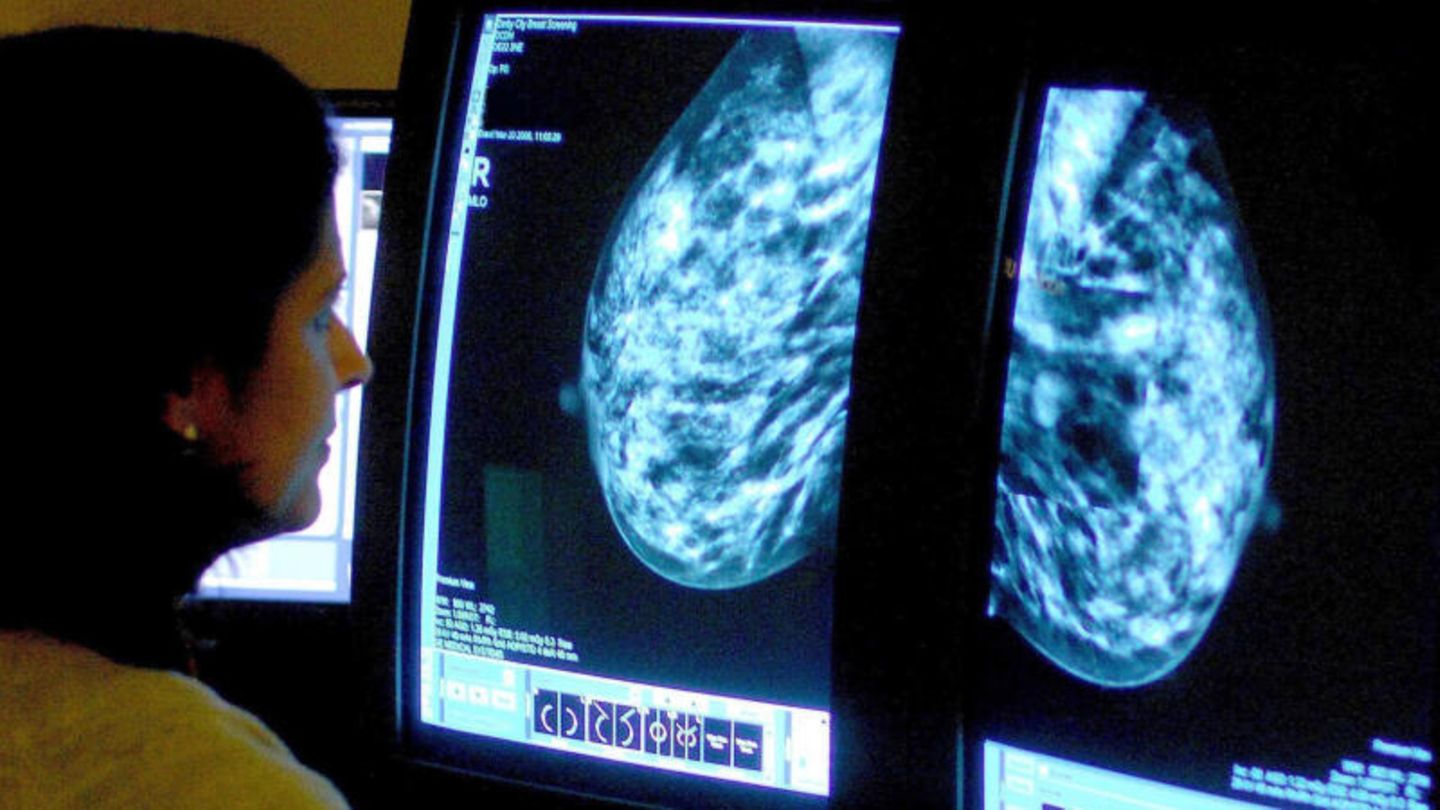

In den drei Jahrzehnten seit 1990 ist die Zahl der Krebsdiagnosen bei unter 50-Jährigen weltweit um fast 80 Prozent gestiegen. Die meisten der 2019 erfassten Fälle entfielen auf Brustkrebs, berichtet eine internationale Forschungsgruppe im Fachblatt "BMJ Oncology". Die schnellste Zunahme binnen der drei Jahrzehnte wurde demnach bei den Fallzahlen für Luftröhren- und Prostatakrebs verzeichnet. Gesunken sei in der untersuchten Alterskohorte die Zahl erfasster Leberkrebserkrankungen, um knapp drei Prozent. Auf Deutschland ist die Analyse einem deutschen Experten zufolge nicht direkt übertragbar.

Für die Analyse griff das Team um Xue Li von der chinesischen Zhejiang University School of Medicine in Großbritannien auf die 2019er-Ausgabe der Studienserie "Global Burden of Disease" zurück. Sie enthält zwischen 1990 und 2019 erhobene Daten für 29 Krebsarten in 204 Ländern und konzentriert sich dabei auf die 14- bis 49-Jährigen. Bei ihnen wurden demnach 2019 insgesamt 3,26 Millionen neue Krebsdiagnosen gestellt – ein Anstieg von 79 Prozent im Vergleich zu 1990.

Insgesamt starben 2019 mehr als eine Million Menschen unter 50 Jahren an Krebs, was einem Anstieg um knapp 28 Prozent im Vergleich zu 1990 entspricht. Die meisten Todesfälle waren bei Brust-, Luftröhren-, Lungen-, Darm- und Magenkrebs zu beklagen, wobei die Todesfälle bei Nieren- und Eierstockkrebs am stärksten zunahmen. Geografisch zeigten sich die höchsten Raten an Krebserkrankungen in Nordamerika, Australasien und Westeuropa, doch auch in Ländern mit niedrigem bis mittlerem Einkommen stiegen die Fallzahlen und das vor allem bei Frauen.